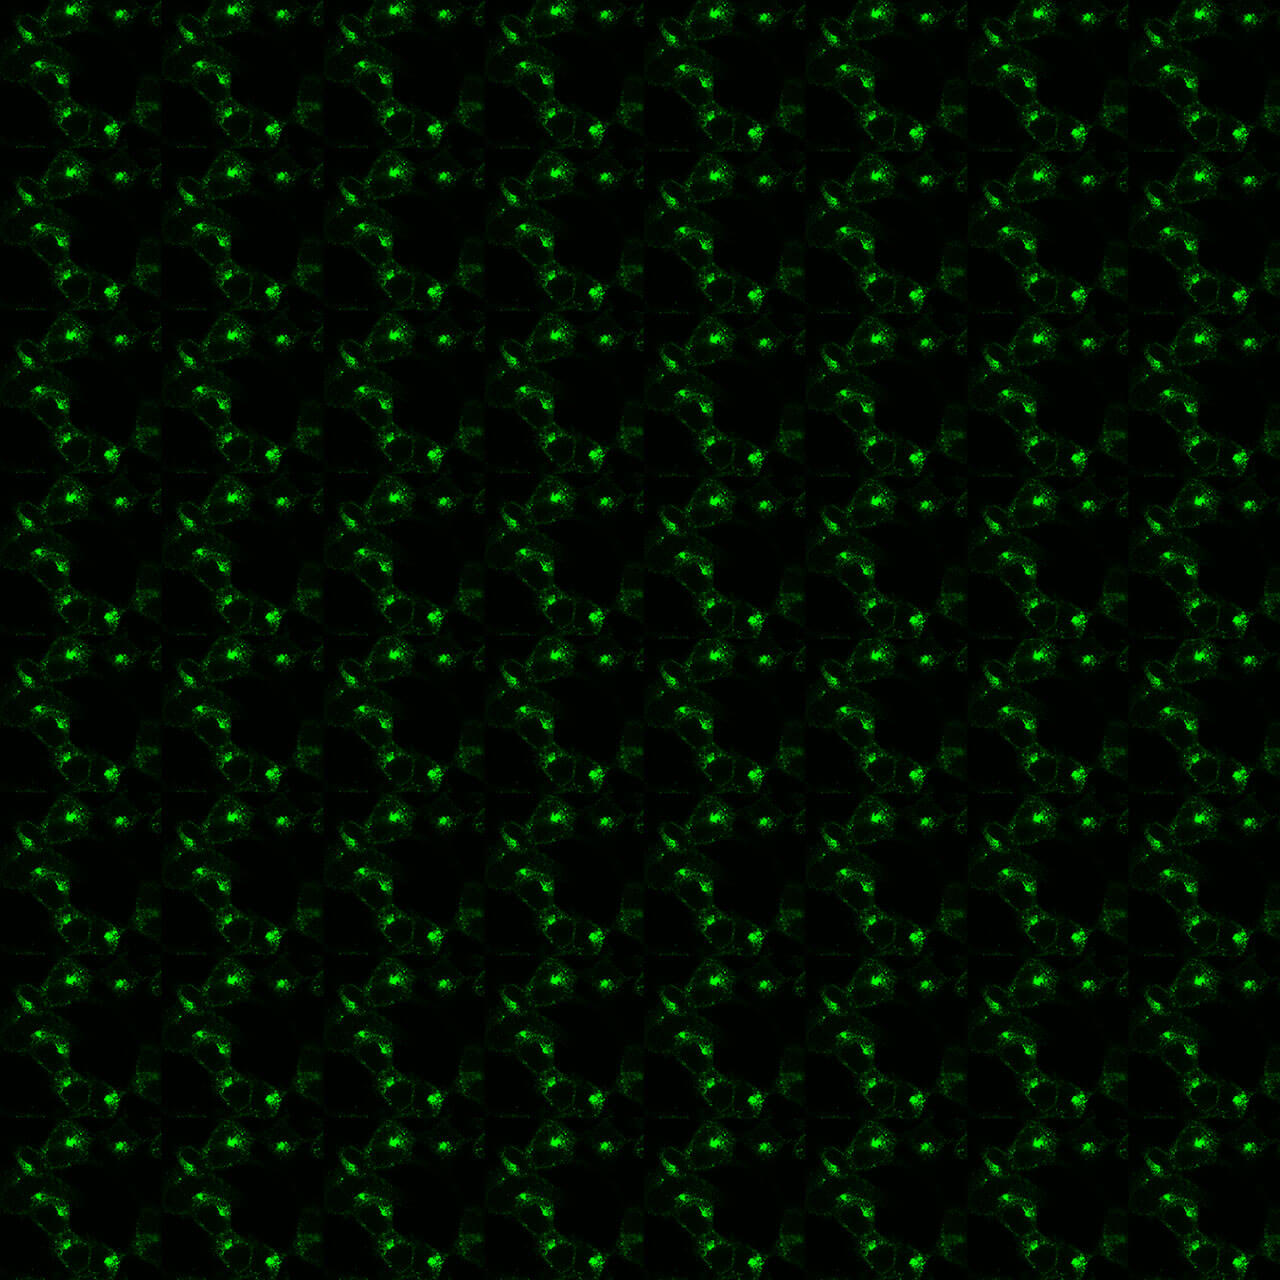

Figure 1. Validation of the M1 Muscarinic Acetylcholine Receptor in transfected HEK293 cells. Native HEK293 cells (MOCK) or HEK293 cells stably expressing the M1 Muscarinic Acetylcholine Receptor (M1) were lysed and immunoblotted with the phosphorylation-independent anti-M1 antibody (7TM0013N) at a dilution of 1:1000.